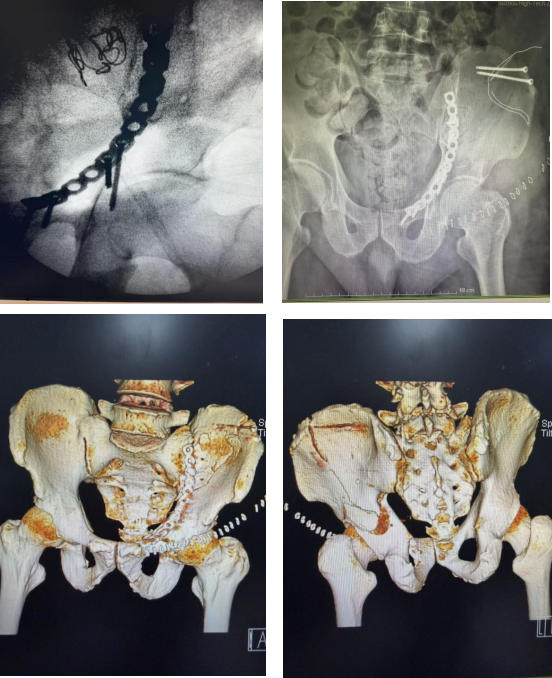

从“破碎”到“完整”:苏高医骨科助力200余斤复杂髋臼双柱粉碎性骨折患者康复

近日,苏州高新区人民医院骨科成功为一名体重达200余斤的复杂髋臼双柱粉碎性骨折患者精准实施复位内固定手术。 面对患者超常体重与复杂骨折的双重挑战,骨科团队在多学科协作下以精湛的技术顺利完成该手术。目前,患者恢复良好。

创伤骨科王玉方主任介绍,髋臼是连接躯干与下肢的“承重之桥”,其骨折因解剖位置深、毗邻重要神经血管、复位固定要求高,历来是骨科创伤治疗的难点。此次收治的患者因车祸导致髋臼前柱与后柱粉碎性骨折——这意味着其髋关节的“碗状”结构已完全碎裂、移位。更为棘手的是,患者体重达200余斤,厚重的软组织层给手术视野带来极大困难,术后骨骼需承受的超常负重,对内固定物的力学强度提出严苛要求;同时,因患者体重偏大也显著增加了深静脉血栓、感染等并发症风险。

面对挑战,骨科团队进行了详细的术前评估,决定采用经典的髋腹股沟入路。术中,由贾鹏主任医师主刀,将粉碎的骨块逐一精准复位。复位完成后,团队采用特制钢板与螺钉系统进行坚固内固定,为碎裂的骨骼搭建起足以支撑早期康复锻炼的“内部脚手架”。整台手术出血量极少,且有效保护了神经。